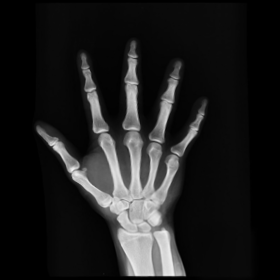

7.2. Real X-ray images

After testing our proposed method on several synthetic images, we now consider applying it on real medical images. Here, we consider a hand X-ray image as the source image (Fig. 7(a)) and a deformed hand X-ray image as the target image (Fig. 7(b)). Fig. 7(c) shows the original absolute intensity difference between the two images. It can be observed that different fingers are displaced in a nonuniform manner (for example, the displacement of the index finger is much larger than that of the little finger), while the wrist remains almost the same. Therefore, a simple rigid transformation is insufficient for yielding a good registration. As shown in Fig. 7(d), our proposed method successfully deforms the source image to match the target image, and the final intensity difference is significantly smaller (see Fig. 7(e)). From the deformed underlying grid in Fig. 7(f), it can be observed that the mapping is smooth and bijective. For comparison, both LDDMM [5] and DDemons [47] fail to register the fingers and are non-bijective (see Fig. 7(g), Fig. 7(h), and Fig. 7(i)).